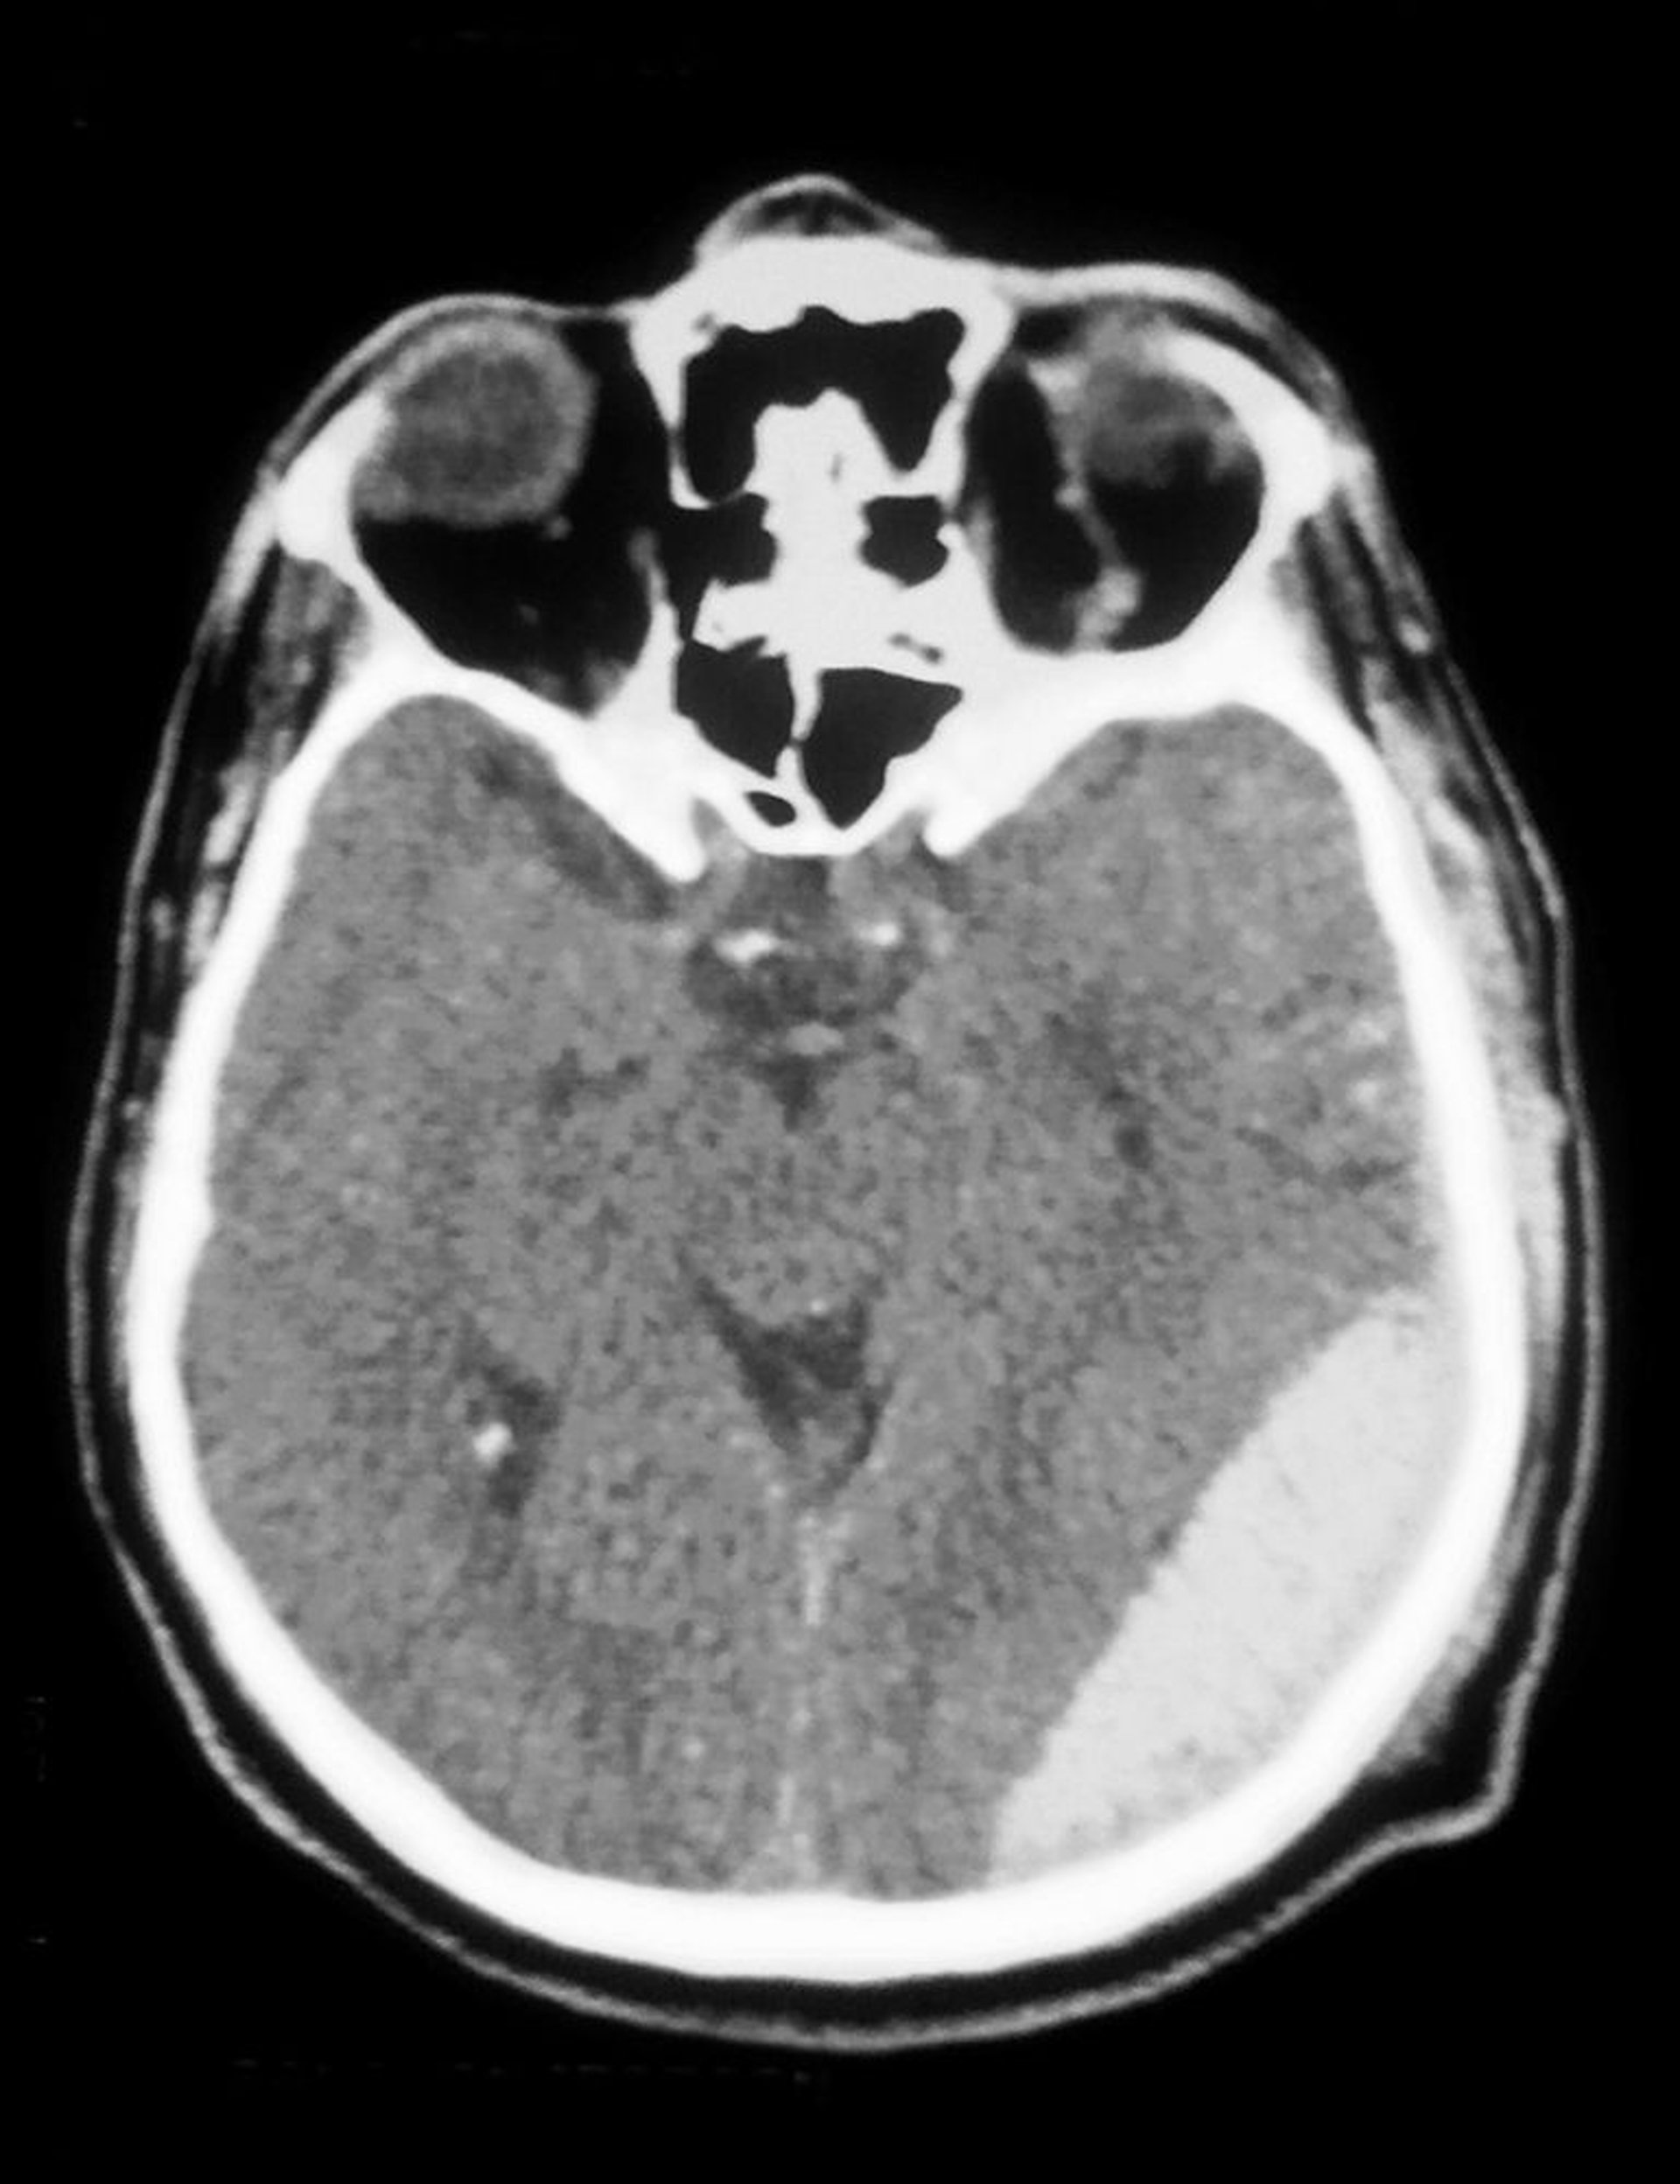

La TC muestra un hematoma epidural (opacidad en la parte inferior derecha).

Hematoma epidural